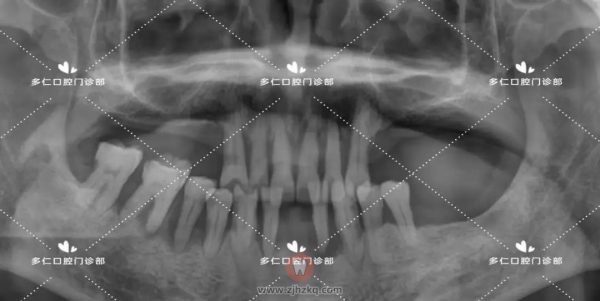

术前CBCT照片如下